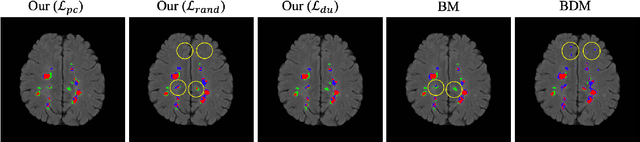

Abstract:This paper presents a simple and effective generalization method for magnetic resonance imaging (MRI) segmentation when data is collected from multiple MRI scanning sites and as a consequence is affected by (site-)domain shifts. We propose to integrate a traditional encoder-decoder network with a regularization network. This added network includes an auxiliary loss term which is responsible for the reduction of the domain shift problem and for the resulting improved generalization. The proposed method was evaluated on multiple sclerosis lesion segmentation from MRI data. We tested the proposed model on an in-house clinical dataset including 117 patients from 56 different scanning sites. In the experiments, our method showed better generalization performance than other baseline networks.